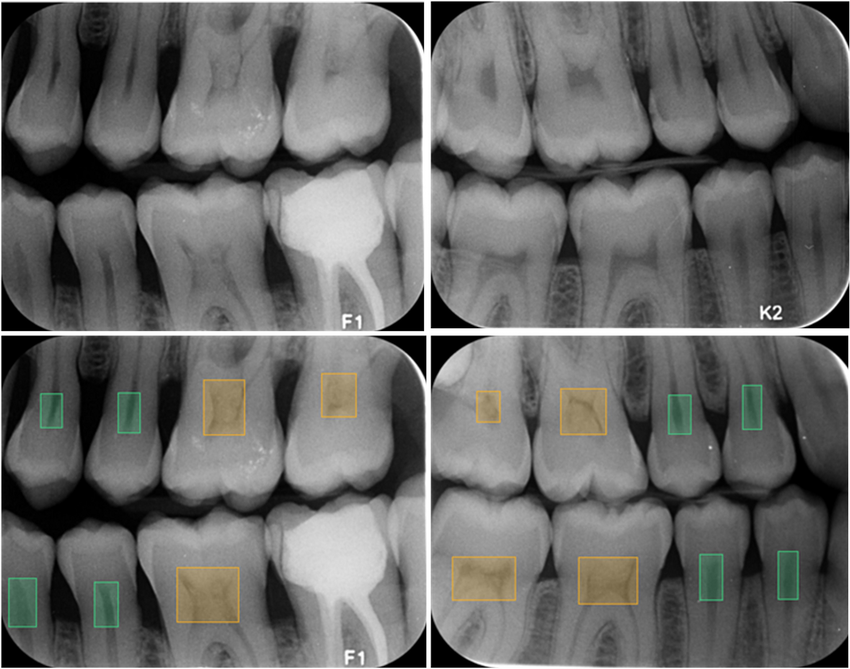

Bite wing snimka s ugrizom u traku je tehnika snimanja kruna

Pretkutnjaka i kutnjaka.

Ova relativno jednostavna tehnika snimanja zuba pomaže u dijagnostici karijesa na kontaktnim točkama susjednih zuba.

To su dijelovi zuba na kojima se uobičajenim postupcima ne mogu

Detektirati karijesi koji su još u začetku.

Ova tehnika bi trebala biti standardni postupak pri kontroli zuba.